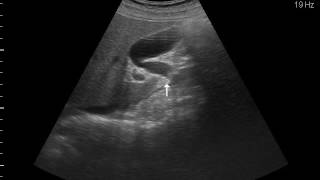

病院で胆石があるといわれ、そのまま入院となった。大きな石が2個エコー検査で写っている。胆嚢を摘出するのが完治になるそうだが、この時は胆のう炎を起こしているため、脇腹から炎症を起こしている胆汁を抜くことになった。この時は、石を残したまま、退院した。が、しかし、一か月も経たないうちに、再入院することになった。一週間ほど、熱があがったり、さがつたり、悪寒や嘔吐があったりしていたので、かかりつけの先生もこれは風邪ではなく、胆のう炎からきているということで前回の病院へ入院した。今回は、腹腔鏡下胆嚢摘出術で胆嚢ごと石も摘出した。